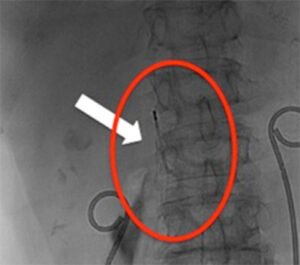

È un “ombrellino” che viene posizionato in vena cava inferiore e serve a proteggere dalla

eventuale migrazione di trombi provenienti dal sistema venoso profondo degli arti

inferiori (in caso di trombosi venosa profonda degli arti inferiori) o dalle vene

iliache e/o dalla vena cava inferiore sotto-renale.Questo può essere posizionato dal Radiologo Interventista sotto guida radiologica, in

maniera abbastanza semplice, sia con approccio dalla vena femorale comune (inguine),

che dalla vena giugulare interna (collo), che dalla vena brachiale (braccio) e dalla

vena poplitea.Questo ombrellino è removibile, quindi nel momento in cui il rischio di migrazione dei

trombi è stato risolto (per esempio quando il Paziente guarisce dalla trombosi venosa

profonda), può essere rimosso dal Radiologo Interventista, sotto guida radiologica, con

accesso dalla vena giugulare interna (collo) e un kit dedicato, fornito dalle case

produttrici del filtro.